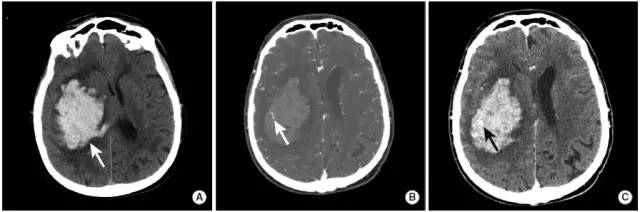

图7

本例高血压性脑出血患者具有典型的“点状征”表现。

图A:CT平扫显示右侧基底节区大量脑出血(长尾箭头)。

图B:CTA扫描动脉期显示点状高密度影(长尾箭头),即“点状征”。根据“点状征”的定义,点状强化为血肿边缘与血管不相连的高密度灶。

图C:CTA扫描延迟期显示活动性出血灶中与图B相同位置的高密度影(长尾箭头)。